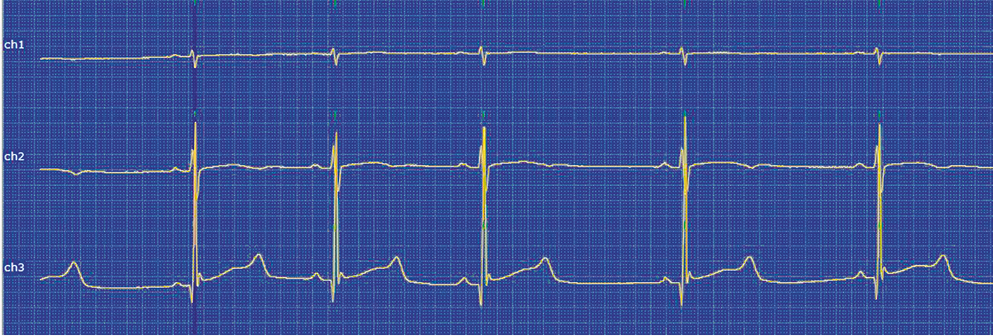

During ECG HM, a prolongation of the QT interval up to 680 ms was registered (Fig. 3).

Fig. 3. Fragment of Holter ECG monitoring in young athlete A. The maximum duration of the QT interval

The QT interval prolongation persisted regardless of the HR, namely, 680 ms in sinus rhythm with an HR of 53 beats/min, 580 ms with an HR of 85 beats/min (Fig. 4), and with a norm according to ECG HM findings up to 480 ms [9].

Fig. 4. Fragment of Holter ECG monitoring in young athlete A. Prolongation of the QT interval